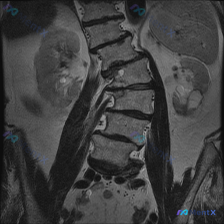

整理到一张腰椎MRI-T1序列冠状位的影像资料,先不说是啥结论,大家看看第一眼会怎么考虑? 现有影像能看到的点: 1. 腰椎明显向右侧弯畸形 2. 多节段椎间隙变窄,下腰段(L4-L5、L5-S1)更明显,边缘有骨赘 3. 各腰椎椎体信号不均匀,里面有散在的、片状/斑点状的T1低信号影(对比周围的高...

整理到一份腰椎MRI T1加权像冠状位的影像分析资料,先不说最终倾向,把核心发现放出来大家讨论下: 核心影像表现: 1. 脊柱:明显腰椎右侧凸畸形,椎体边缘骨质增生、部分模糊,椎间隙左右不对称、部分狭窄,椎间盘T1信号广泛减低;小关节间隙窄、关节突肥大,凹侧结构紊乱。 2. 骨髓信号:关键! 椎体骨...